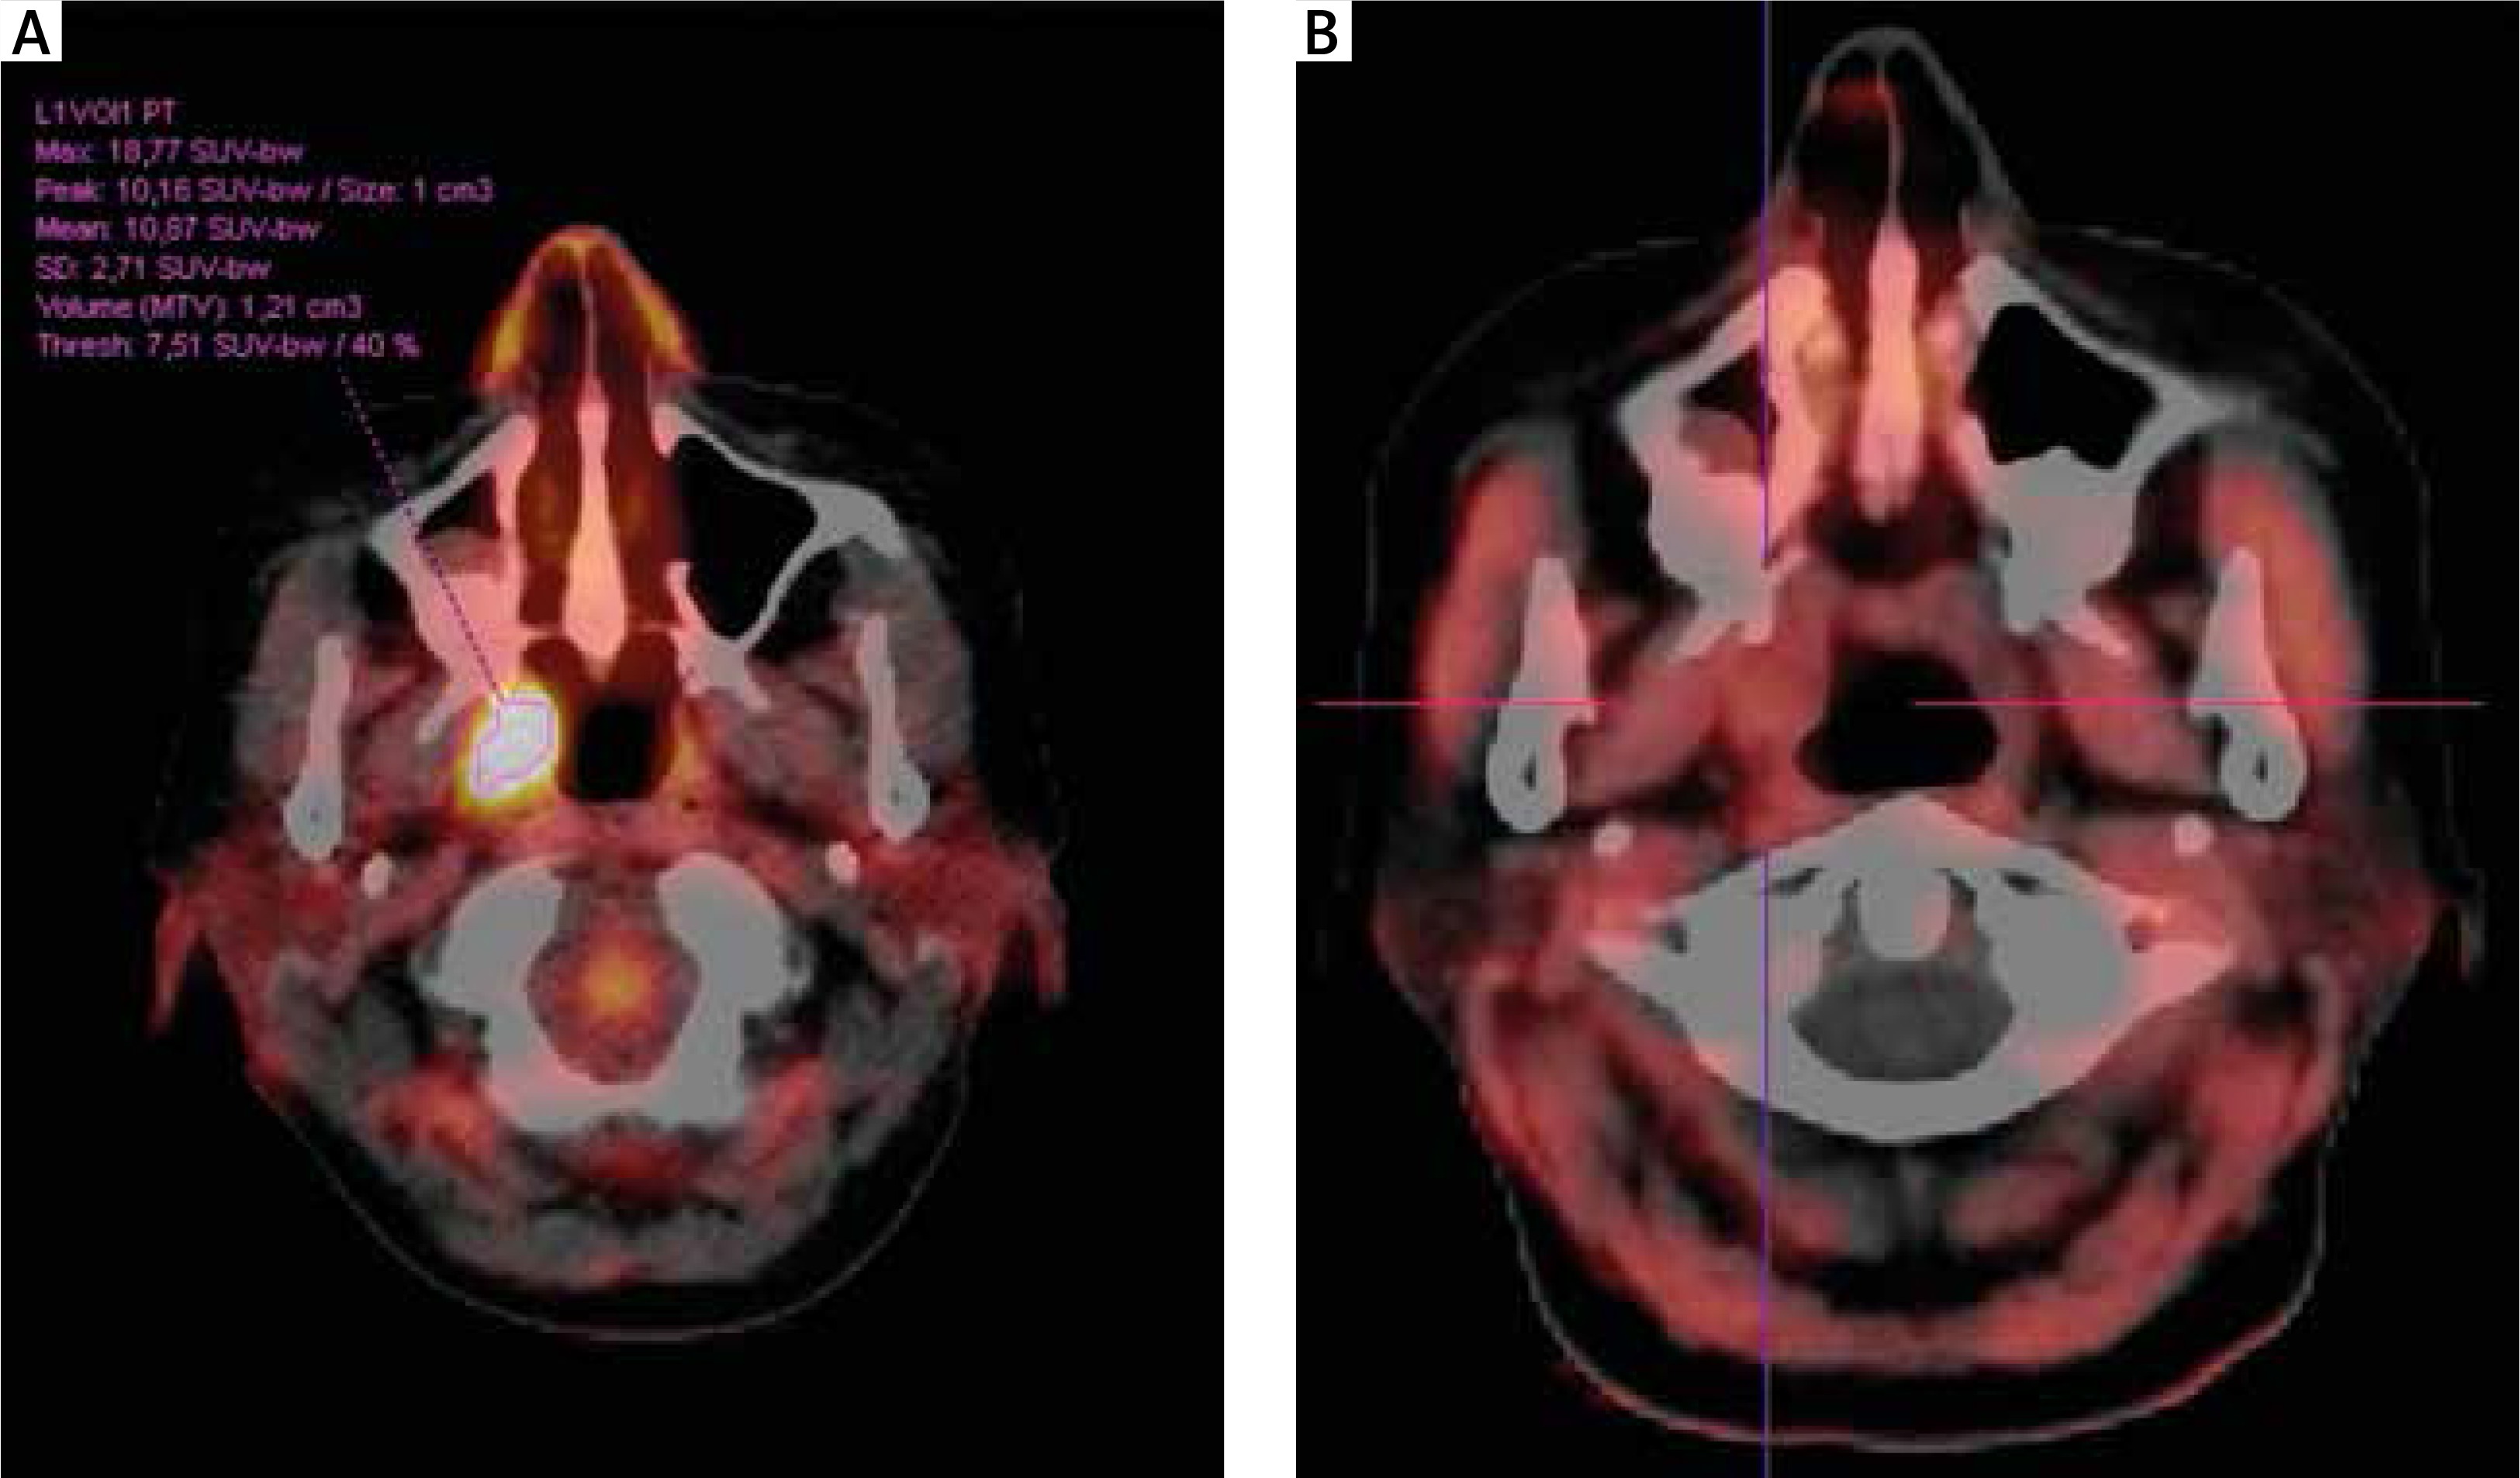

Fig. 4

Patient no. 32. A) Solitary myeloma lesion suspected in the right palatine tonsil, positive in FDG PET/CT, showing high uptake SUVmax 18.77. B) Negative FET PET/CT result showing no tracer uptake in the right tonsil. No subsequent clinical progression of myeloma was observed on further follow-up

Patients with CR and VGPR had no FET-positive lesions. One of the patients in CR, according to the assessment of the treating physician, had an equivocal lesion on CT, which was positive on standard PET with fluorine-labelled deoxyglucose (2-deoxy-2-[18F]fluoro-D-glucose [18F-FDG]) used as a tracer. Subsequent examination with 18F-FET tracer did not reveal any activity (Fig. 4). Obviously, the biopsy of the affected area could not be performed.